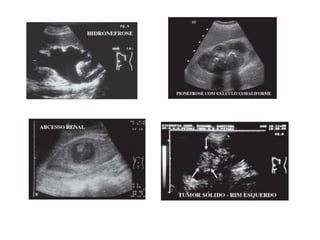

Ultra-sonografia

• Indicações:

 Obstruções do sistema coletor

 Nefrolitíase

 Distinção entre lesões císticas e sólidas

 Avaliação vascular

 Biópsia renal

• Limitações: ar, osso e tecido adiposo.

Ultra-sonografia • Indicações:  Obstruçõesdo sistema coletor  Nefrolitíase  Distinção entre lesões císticas e sólidas  Avaliação vascular  Biópsia renal • Limitações: ar, osso e tecido adiposo.